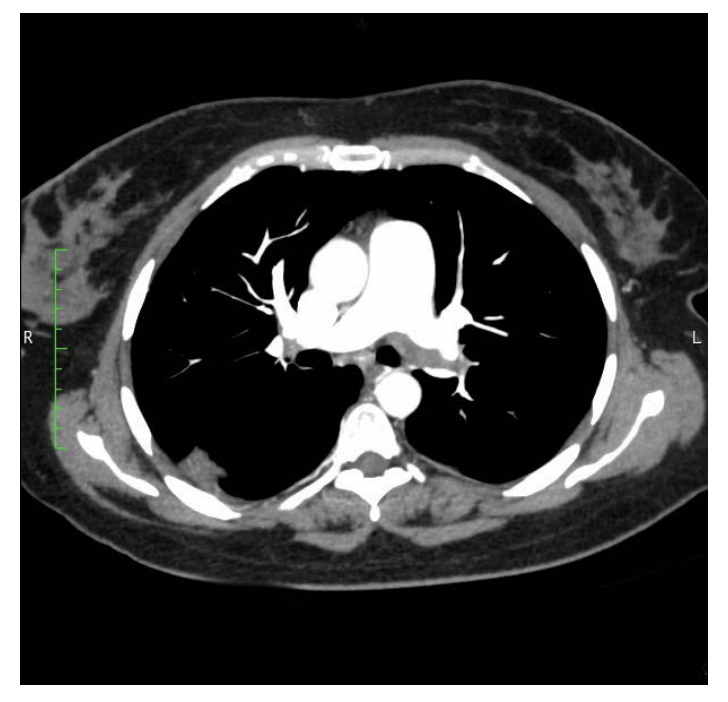

A 46-year-old female patient presented to the emergency unit with clinical symptoms and signs of left acute lower limb ischemia. The patient had no risk factors for atherosclerosis like diabetes mellitus, hypertension, hyperlipidemia, or smoking, and no history of coronary artery disease. Two months prior to this presentation she had a stroke with dysarthria, dysphagia, and right sided weakness that lasted for 2 days and she was started on aspirin. In the emergency room she was hemodynamically stable, and the left foot was painful, cold, pale, weak, and pulseless. The basic labs were normal, and the ECG showed no arrhythmias. She had a CT angiography which showed total occlusion of the left iliac and femoral arteries with reconstitution of blood flow to the popliteal artery (Figure 1). She was transferred to the operating room and underwent a successful thromboembolectomy with return of blood flow to the limb. Post operatively, the patient had transthoracic and transesophageal echocardiography and CT angiography of the chest, head, and neck. The echocardiography showed a patent foramen ovale and a right ventricular thrombus 2 cm in size. It also showed pulmonary hypertension with a right ventricular systolic pressure of 50 mmHg. The CT of the chest showed large, massive filling defects in the main and primary branches of both pulmonary arteries, representing massive PE (Figure 2). The CT of the head showed filling defect in the confluence of the superior sagittal sinus extending to the left transverse sinus, concerning for venous thrombosis with normal carotid and vertebral arteries. Lower limbs venous doppler was negative for deep venous thrombosis. Thrombophilia workup was negative except for reduced Antithrombin III level possibly due to heparinization.